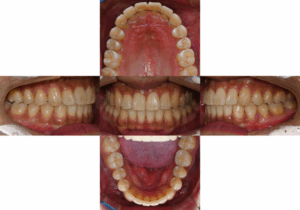

반갑습니다, 면목역 치과 글로리의 김정은 대표원장입니다. 교정이 필요한 순간들이 꽤 여럿 있습니다. 가지런하지 못한 치열을 가졌을 때도 있고, 때로는 맞지 않은 교합 관계의 문제, 그리고 뻐드러진 치열을 가질…